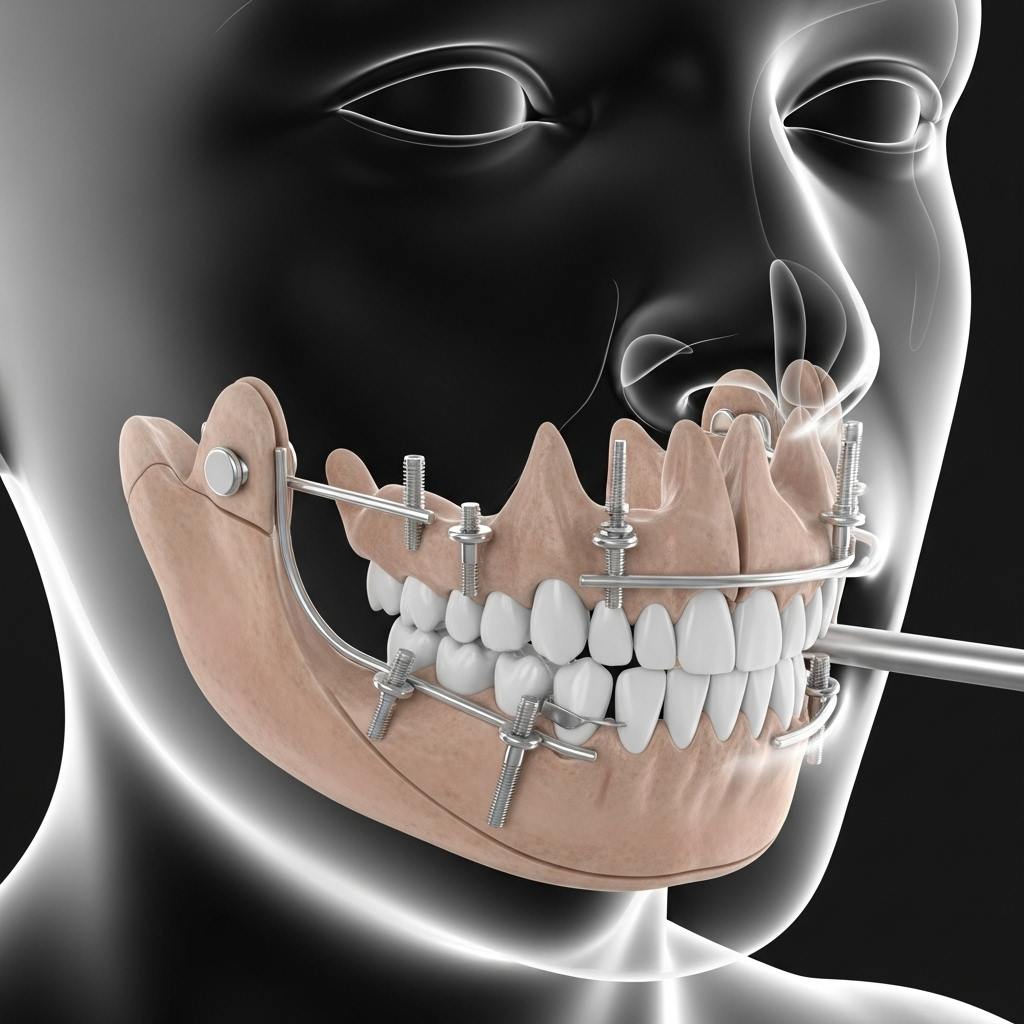

Ağız ve maksillofasiyal cerrahi, ağız, çene, yüz ve boyun bölgelerini içeren cerrahi prosedürlere odaklanan diş hekimliğinin özel bir dalıdır. Bu kapsamlı alan, yirmi yaş dişi çekimi, diş implantları cerrahisi, düzeltme çene cerrahisi, yüz travması rekonstrüksiyonu, ağız patolojisi tedavisi ve temporomandibular eklem (TMJ) cerrahisi dahil olmak üzere geniş bir prosedür yelpazesini kapsar. Ağız cerrahisi, gömülü dişler, şiddetli diş enfeksiyonları, çene yanlış hizalanması, yüz yaralanmaları veya ağız tümörleri gibi karmaşık sorunları konvansiyonel diş tedavileri ele alamadığında gereklidir. Deneyimli cerrahlarımız hem rutin prosedürleri hem de karmaşık rekonstrüktif cerrahileri ele almak üzere eğitilmiştir, çeşitli cerrahi ihtiyaçları olan hastalar için optimal sonuçlar sağlar. Hem fonksiyonel hem de estetik kaygıları ele alan kapsamlı bakım sağlamak için diğer diş uzmanları ve tıp profesyonelleriyle yakın işbirliği yaparız.

Optimal sonuçlar ve minimal hasta rahatsızlığı sağlamak için en gelişmiş cerrahi teknikleri ve son teknolojiyi kullanıyoruz. Cerrahi protokollerimiz, çevredeki dokulara travmayı azaltan ve daha hızlı iyileşmeyi teşvik eden minimal invaziv prosedürleri içerir. Minimal ısı üretimi ile hassas kemik kesimi için piezoelektrik kemik cerrahisi, azaltılmış kanama ve şişlik ile yumuşak doku yönetimi için lazer destekli prosedürler ve maksimum doğruluk ve öngörülebilirlik için bilgisayar destekli implant yerleştirme kullanıyoruz. Cerrahi süitimiz, hasta güvenliğini sağlamak için son teknoloji izleme ekipmanları, gelişmiş görüntüleme sistemleri ve acil durum protokolleri ile donatılmıştır. Uygun olduğunda IV sedasyon ve genel anestezi dahil olmak üzere modern anestezi teknikleri kullanıyoruz, prosedür boyunca deneyimli anestezi profesyonelleri tarafından sürekli izleme ile.